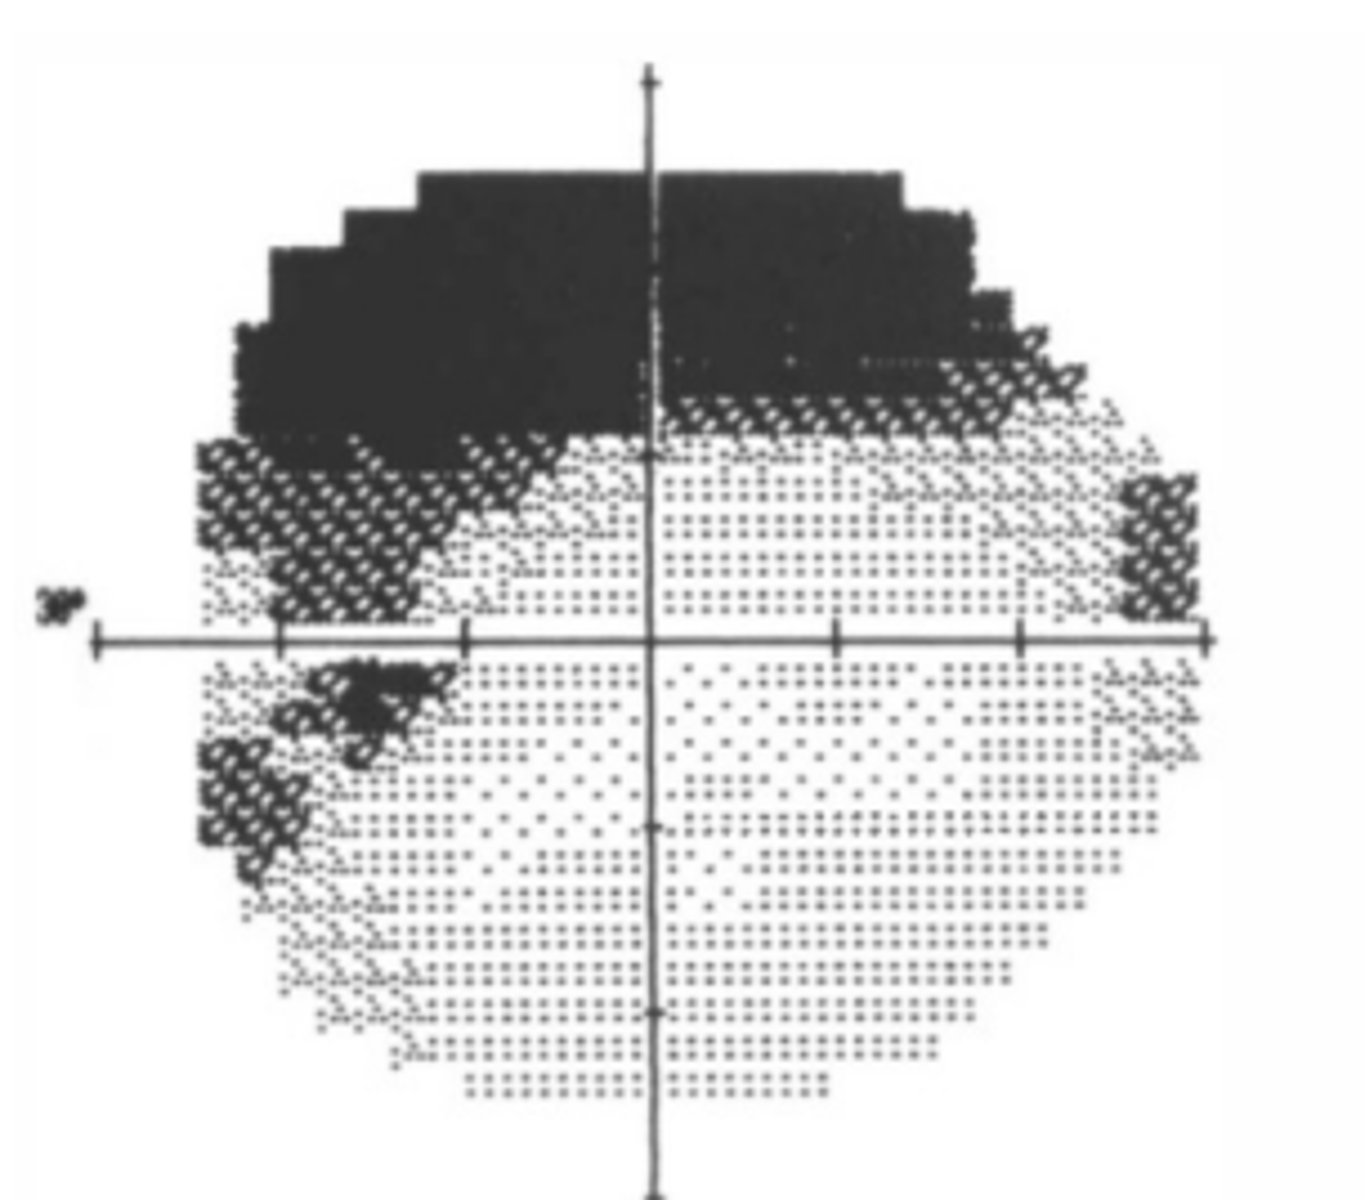

superiorly

Dermatochalasis will show a visual field defect...

Grayscale

presentation of VF results that gives a visual representation of sensitivity. Is useful for detecting artifacts and overall regions of concerns, but should not be used to assess the actual defect in detail.